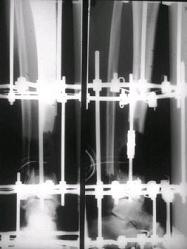

отделяемое. #1;#2. Стержневой апп. снят, наложен апп. Илизарова, дренажно

ирригационная система промывки раны. #3; #4. После стихания инфекции,

аппаратом постепенно создана рекурвация для сближения контактов мышц

(сухожилий) передней группы голени. #5;#6. Наложен шов на сухожлилия М.